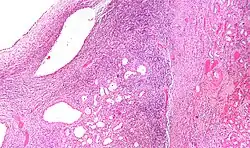

| Micrograph of a cystic nephroma (left of image). Normal kidney is seen on the right. H&E stain. | |

The characteristics of cystic nephromas are:

- Cysts lined by a simple epithelium with a hobnail morphology, i.e. the nuclei of the cyst lining epithelium bulges into the lumen of the cysts,

- Ovarian-like stroma that has a:

- Spindle cell morphology, and has a

- Basophilic cytoplasm.